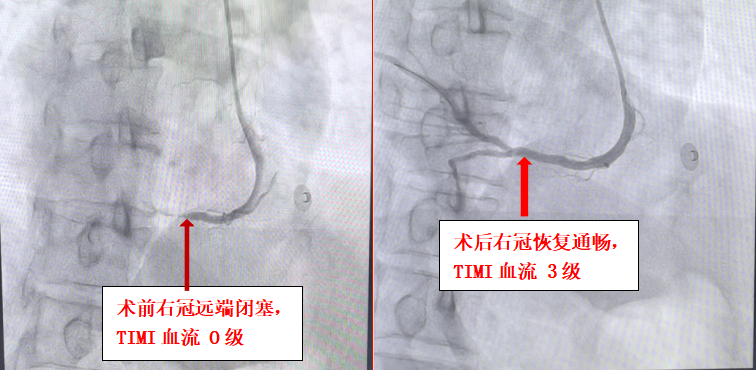

术中造影证实,患者供血心脏下壁的右冠状动脉中远段完全闭塞,TIMI血流0级,这正是此次心梗的“元凶”。在X光影像的引导下,手术团队屏气凝神,小心翼翼地操控着导丝,如同在镜面中倒车,精准地通过闭塞段。面对闭塞处的高血栓负荷,团队果断采取冠脉内溶栓,待血栓负荷减轻后,顺利植入支架。当造影剂再次通过血管,原本堵塞的血管瞬间恢复畅通,患者胸痛症状立即缓解,生命体征逐渐趋于平稳,手术成功了!术后患者被转入心内科二区CCU病房进一步观察,目前恢复情况良好。